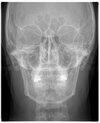

Hey guys, I’m new here so sorry if I sound dumb, just trying to learn. I’m 25 and really insecure about my side profile. My bite’s fine but my chin looks weak and kinda tucked back, with a small pouch of fat under it.

Would losing weight help or is it more of a chin/jaw issue that needs surgery like genio or LJS/DJS? I’d appreciate any honest advice or similar experiences.

i think you might need jaw advancement, genio would help since your frankfurt plane is recessed but bimax would be best